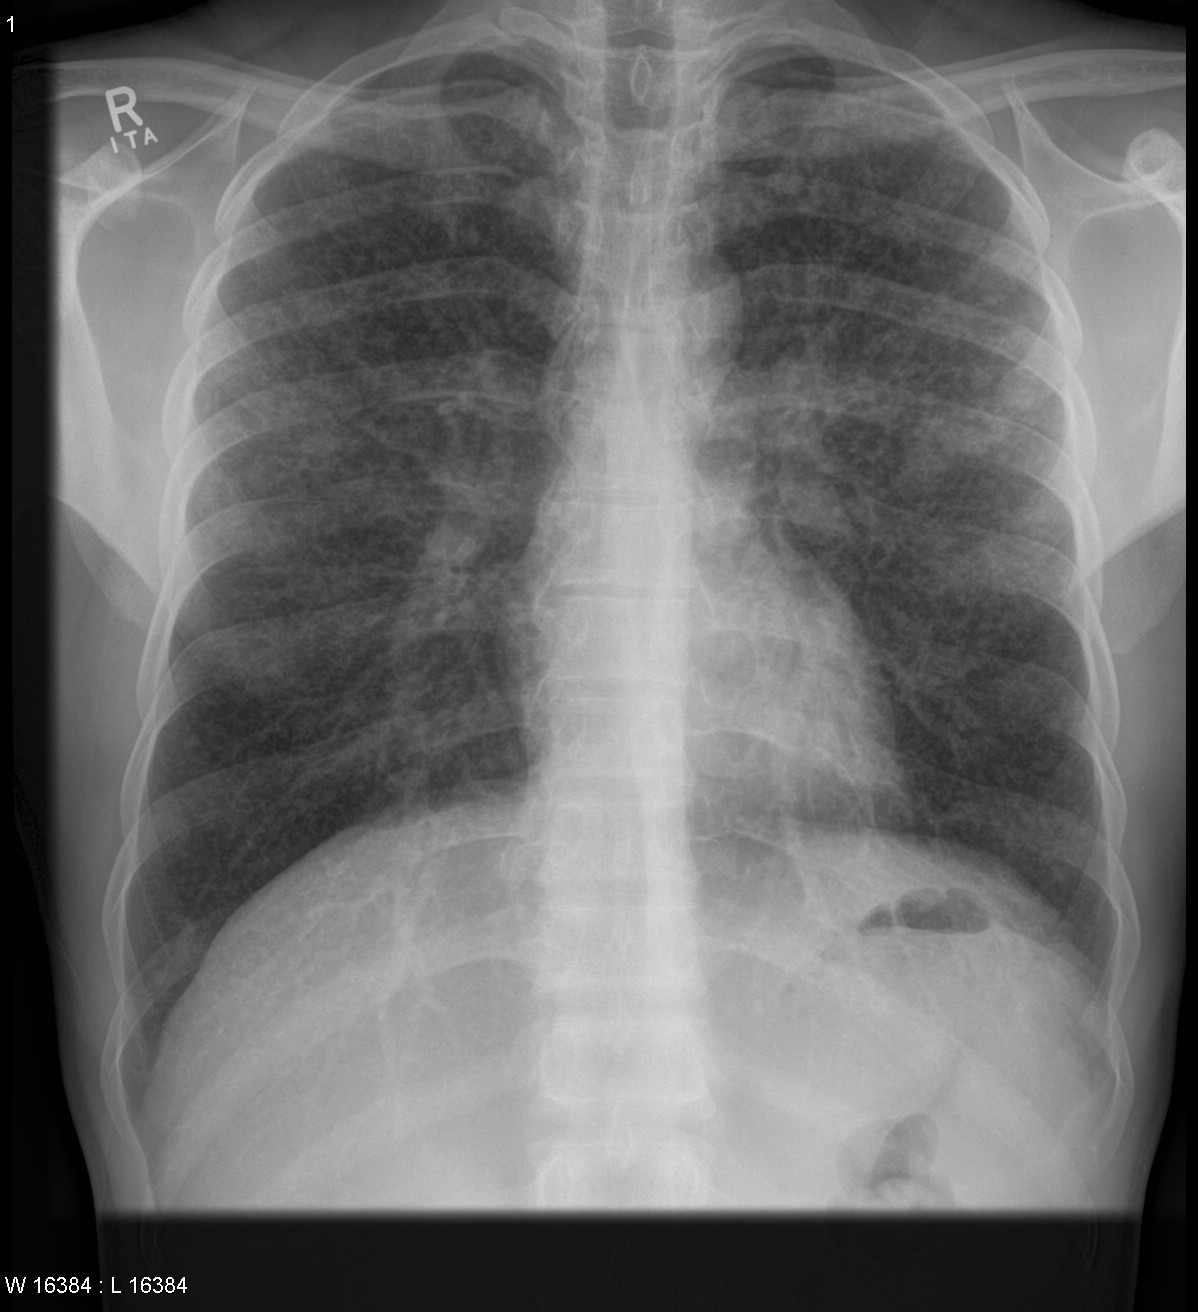

Снимок легких при туберкулезе является важным методом диагностики этого заболевания. На рентгеновских снимках можно увидеть изменения в легких, которые свойственны туберкулезу.

Рентген грудной клетки туберкулез

Рентген грудной клетки туберкулез

Рентгенография грудной клетки туберкулез

25

Рентгенография грудной клетки туберкулез

Рентген грудной клетки туберкулез

Рентген грудной клетки туберкулез

Фотографии снимков легких при туберкулезе

В данной статье представлены многочисленные фотографии снимков легких при туберкулезе, чтобы помочь вам понять, как выглядят изменения легких на рентгеновских снимках при этом заболевании.